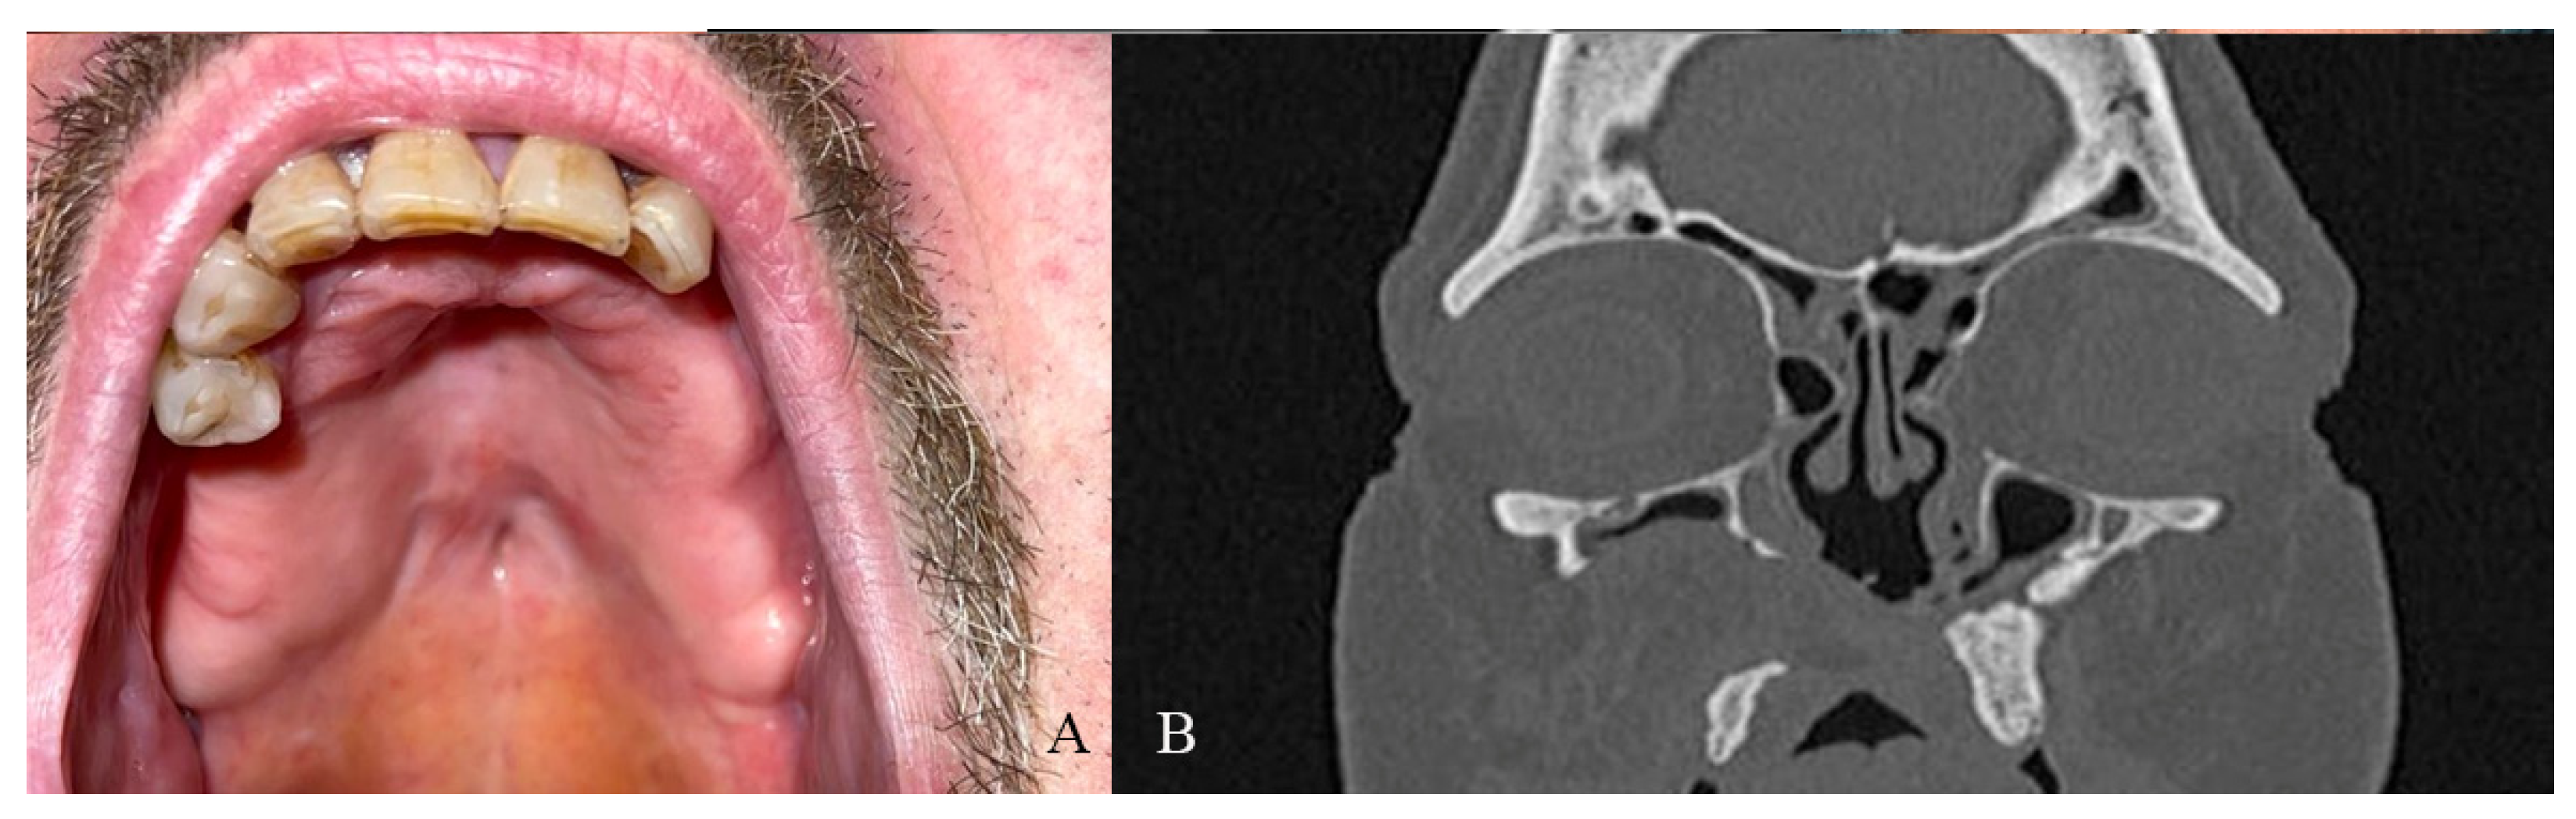

A 49-year-old female patient came to our attention in 2021, presenting a palatal/oro-nasal fistula measuring 2 cm in diameter along the major axis and with atrophic and burned soft tissue surrounding the lesion (Ia according to the Okay et al. classification [14]).

The patient was treated with an obturator to permit correct speech and feeding. At the clinical and radiographic examination, there was also wide, bony, and cartilaginous septal destruction with communication of the nasal cavity and collapse of the nasal pyramid. Speech disturbances, rhinolalia, and eating difficulties were observed (Figure 1).

Figure 1. (A,B) Clinical presentation of the oro-nasal communication. In inset (A), it is possible to appreciate the collapse of the nasal pyramid. (C,D) Radiographic and 3D reconstruction using InVivo6® and Anatomage Table EDU vers.8® (Santa Clara, CA, USA) software. DICOM files were imported in InVivo6® (Santa Clara, CA, USA) software to obtain the axial, cross, and panorex sections. Afterwards, the DICOM files were imported Anatomage Table EDU vers.8® (Santa Clara, CA, USA) to obtain the 3D rendering.